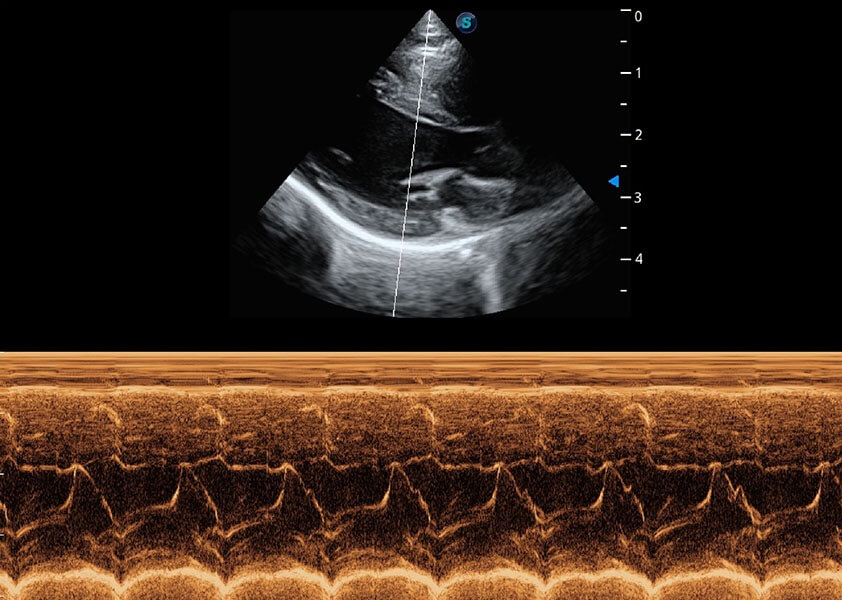

优异的基础图像

(犬)乳头肌短轴

(猫)二尖瓣M型